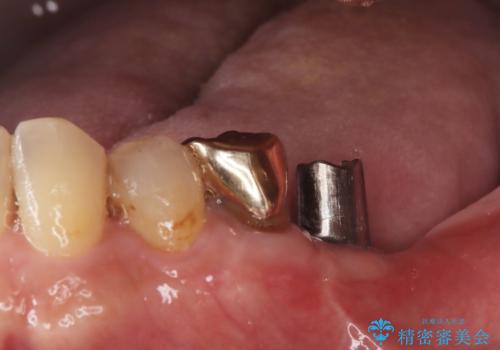

残根状態の歯を抜歯後、抜歯窩の治癒を待ちインプラントを埋入しています。

アバットメントの材質は咬合力を考慮しチタン合金にしました。

被せ物はオールセラミッククラウンを入れています。